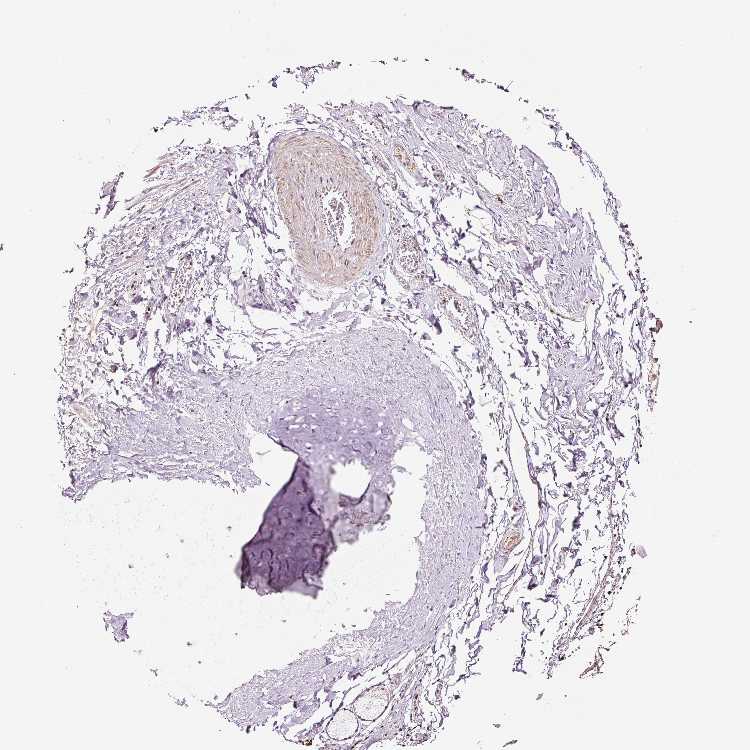

SOFT TISSUE 2 - Antibody stainingi

Antibody staining in the annotated cell types in the current human tissue is reported as not detected, low, medium, or high, based on conventional immunohistochemistry profiling in selected tissues. This score is based on the combination of the staining intensity and fraction of stained cells.

Each image is clickable and will lead to virtual microscopy that enables deeper exploration of all samples and also displays staining intensity scores, fraction scores and subcellular localization as well as patient and tissue information for each sample.

Antibody HPA052130

Chondrocytes Not detected

Fibroblasts Not detected

Peripheral nerve Low